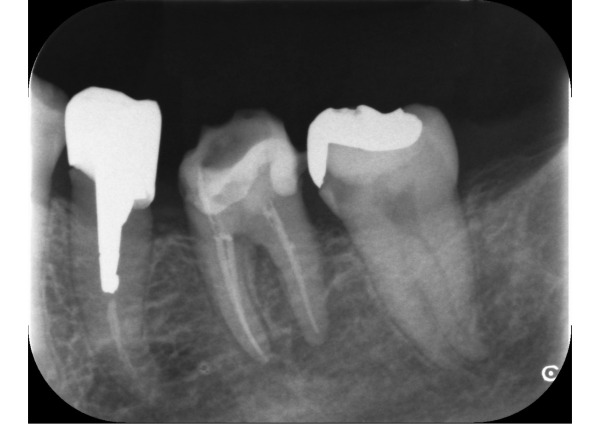

エックス線を撮影すると、右上奥歯2本、左下奥歯2本、左上前歯2本に虫歯が認められました。エックス線写真で診断するより実際は虫歯が深いことがあります。左下6番、左下7番、左上2番の計3本が神経に到達するほどの大きい虫歯でした。

1日目〜5日目 エックス線検査、歯周ポケット検査後、左下の根管治療を始めました。根管充填を完了するまで5回を要しました。

8日目〜12日目 根管治療後、土台をプラスチックで充填し仮歯を装着しました。この時点で、奥歯の被せ物はCADCAM冠(保険適用内)、前歯の左上2番は審美面を考慮してセラミッククラウン(保険適用外)の被せ物をそれぞれ選択いただきました。